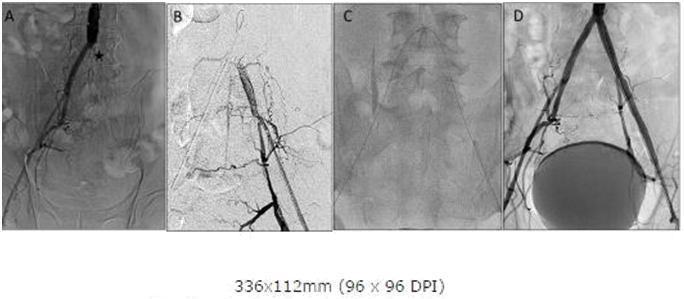

Similar to case 1, Abdominal angiography revealed a left PICTO (Figure 3A) and Lt femoral access was obtained but could not cross the occlusion from below with an 0.035 wire and appeared to enter a dissection plane. A CC was again positioned in the aortic bifurcation (Figure 3B) and a 0.035 glide wire was then slowly advanced through the PICTO from the CC above and the two 0.035 wires lay juxtaposed midway allowing the wire being advanced from below to find the true lumen via the channel of the wire approaching from above (Figure 3C). Once the occlusion was crossed from below and wire position confirmed to be in the true lumen the revascularization was completed with a good angiographic outcome (Figure 3D) and the patient was complication free on follow up at one month.

Figure 3A: Abdominal Aortogram showing Left Common Iliac occlusion and proximal cap (asterisk).

Figure 3B: Angiography from sheath inserted in Left femoral showing distal cap- attempts at wiring from sheath entered subintimal plane.

Figure 3C: Contra catheter with angled glide from right created a channel though which glide wire with Rubicon succeeded in crossing from distal cap. The contra catheter in this case assisted in creating a channel and guiding the wire from the Left.

Figure 3D: Final Abdominal Aortogram after stenting showing good angiographic result.